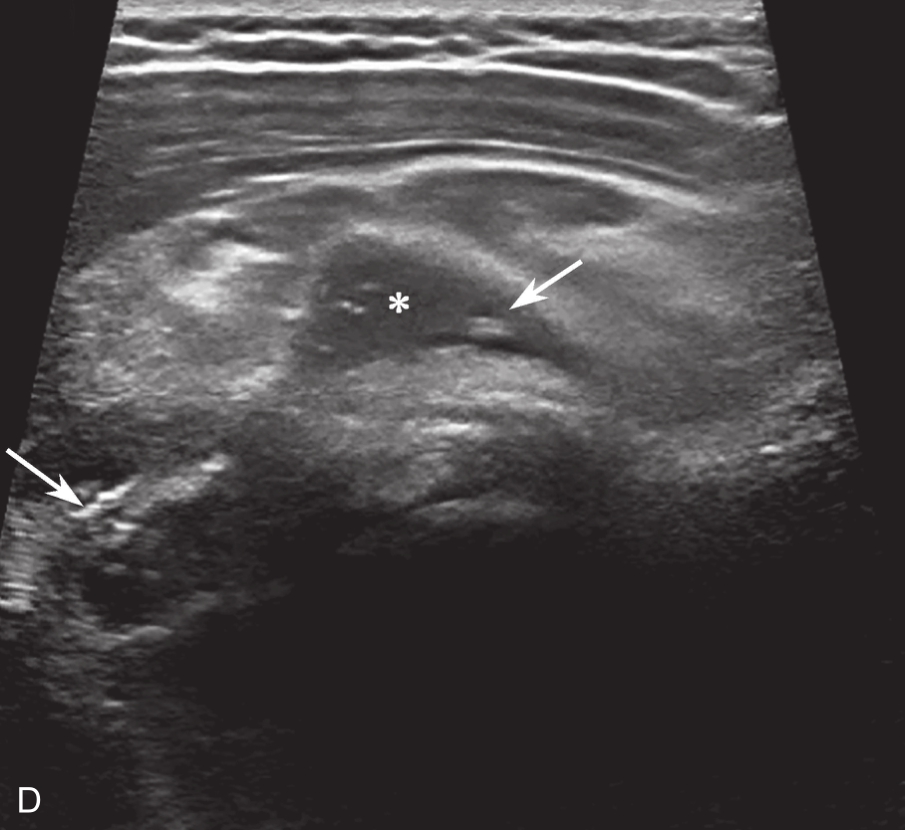

▲ 图 2-6-4(续)

C.超声引导下类固醇及生理盐水注射;D.注射治疗后关节腔扩张;双星号:增厚关节囊;箭头:穿刺针;单星号:关节腔